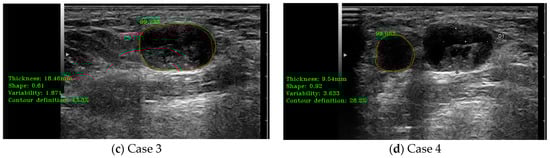

3.4. Elastography Analysis Module Performance Evaluation

In this case, the medical indicators for B-mode US evaluation that were also valid for elastography were kept. Besides those, some specific indicators and algorithms were developed. The specific elastography indicators evaluated some extra parameters like tissue rigidity. The two sub-algorithms for the detection of the B-mode US region and the colored elastography region were also evaluated; the results are presented in Figure 9. In a similar manner to the Doppler analysis module, on the left side of the images are printed, in a green color, the numerical results of several indicators, including the percentage of the analyzed color classes “Red”, “Green”, and “Blue”. For all the cases presented in Figure 9, the combined percentage of “green” and “blue” was above the defined cut-off threshold for metastasis.

Figure 9.

(a–d) illustrate cases of lymph node (LN) automatic detection using elastography, integrating shape parameter evaluation and elastography color indicator assessment for improved diagnostic precision. The red contour represents the manually delineated region by the doctor, while the green contour corresponds to the system’s automatically detected boundary. The percentage value indicates the detection accuracy.